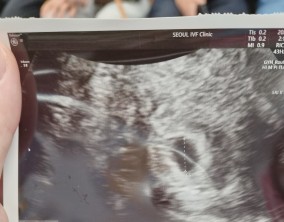

심장소리 이후, 함께 웃게 된 임밍아웃